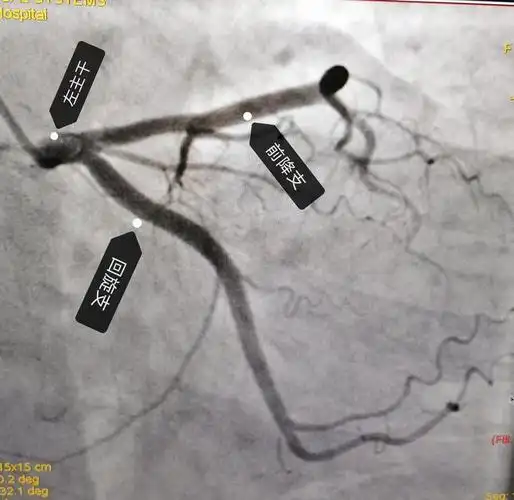

心脏循环有没有狭窄,下面这张图是一个有糖尿病,高血压的患者做的造影

冠脉造影提示:左冠状动脉的前降支也有重度狭窄

冠脉造影显示老杜的心脏血管多处堵塞,病变